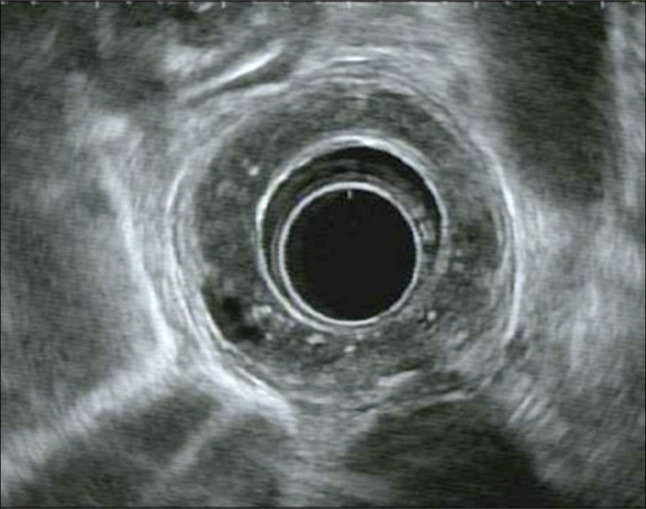

摘要食管壁内假性憩室病(EIPD)是一种罕见的疾病,在内镜下表现为食管壁内有许多小的流出物。虽然通常与吞咽困难等良性症状相关,但EIPD与食管恶性肿瘤有关,既是一种易感疾病,也是相关的共存诊断。然而,两者之间的联系尚不清楚。本病例报告详细介绍了一名有EIPD病史的患者,在整个食管高度发育不良的情况下发展为多灶性浅表鳞状细胞癌。

Esophageal intramural pseudodiverticulosis (EIPD) is a rare disease characterized endoscopically by numerous small outpouchings within the esophageal wall. While typically associated with benign symptoms such as dysphagia, EIPD has been linked to esophageal malignancy, both as a predisposing condition and associated coexisting diagnosis. However, the association is not clear. This case report details a patient with a history of EIPD who developed multifocal superficial squamous cell carcinoma in the context of high-grade dysplasia throughout the esophagus.